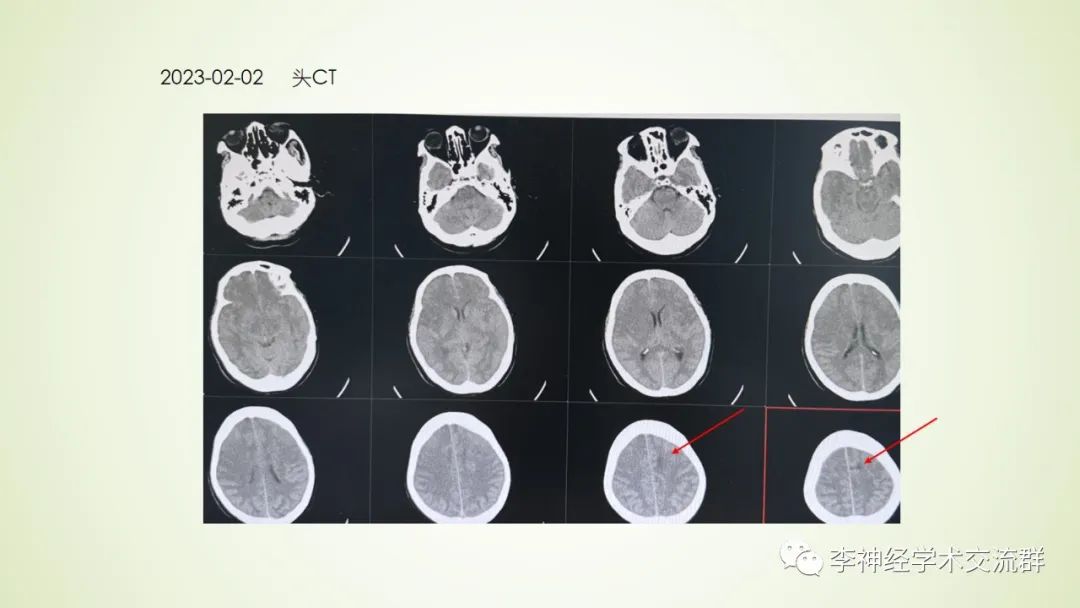

不明脑水肿的病人诊治

作者:台山市人民医院 洪安辉

来源:李神经学术交流群